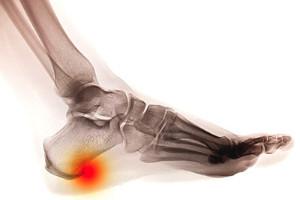

Heel Spurs

Heel spurs are the result of calcium deposits that cause bony protrusions on the underside of the heel. Heel spurs are usually painless, but they have the potential to cause heel pain. Heel spurs tend to be associated with plantar fasciitis, which is a condition that causes inflammation of the band of connective tissue that runs along the bottom of the foot. They most often occur to athletes whose sports involve a lot of running and jumping.

It is possible to have a heel spur without showing signs of any symptoms. However, if inflammation develops at the point of the spur’s formation, you may have pain while walking or running. In terms of diagnosis, sometimes all a doctor needs to know is that the patient is experiencing a sharp pain localized to the heel to diagnose a heel spur. Other times, an x-ray may be needed to confirm the presence of a heel spur.

If you are experiencing a hard lump on the bottom of the heel, you may have what is referred to as a heel spur. It generally comes from calcium deposits and is typically caused by injuries or strains to the foot. If the heel endures pressure, possibly caused by jogging, excess weight, or shoes that fit poorly, heel spurs may gradually develop, often causing discomfort and pain. Other causes of this condition may include having flat feet, standing the majority of the day, or experiencing less flexibility in the plantar fascia which affects the stability of the heel. Possible treatment options may include wearing shoes with a cushioned heel or custom made orthotics. Please schedule a consultation with a podiatrist if you are affected by heel spurs and would like more information.

Heels Spurs

Heel spurs are formed by calcium deposits on the back of the foot where the heel is. This can also be caused by small fragments of bone breaking off one section of the foot, attaching onto the back of the foot. Heel spurs can also be bone growth on the back of the foot and may grow in the direction of the arch of the foot.

Older individuals usually suffer from heel spurs and pain sometimes intensifies with age. One of the main condition's spurs are related to is plantar fasciitis.